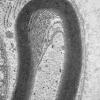

PERIPHERAL NEUROPATHY